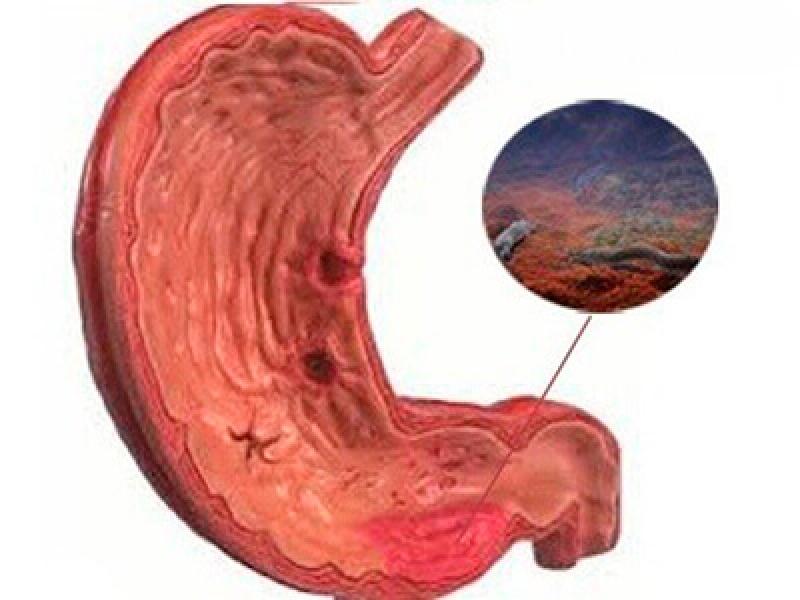

Информация и фотографии о хроническом гастрите и дуодените